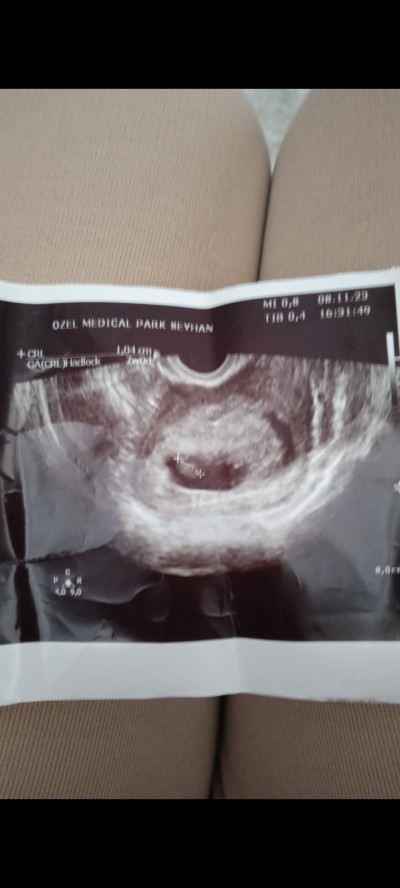

Teoriler varmış bebek küçükken tahmin ediliyor çoğu sayfada denk geldim anlayanlar bakabilir mi vajinal ultrason yapıldı

Gebelik haftası 7